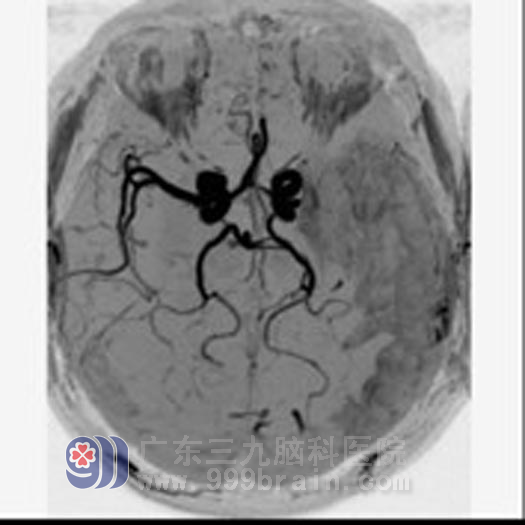

一个半月后复查:

▲ 原梗塞区病变脑软化灶形成,周围胶质增生,相应区域局限性脑萎缩。MRA检查示左侧大脑中动脉仍闭塞。